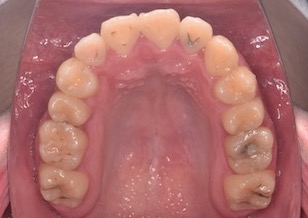

BeforeⅡは、治療前の上顎歯列です。

AfterⅣは、治療終了時の上顎歯列です。